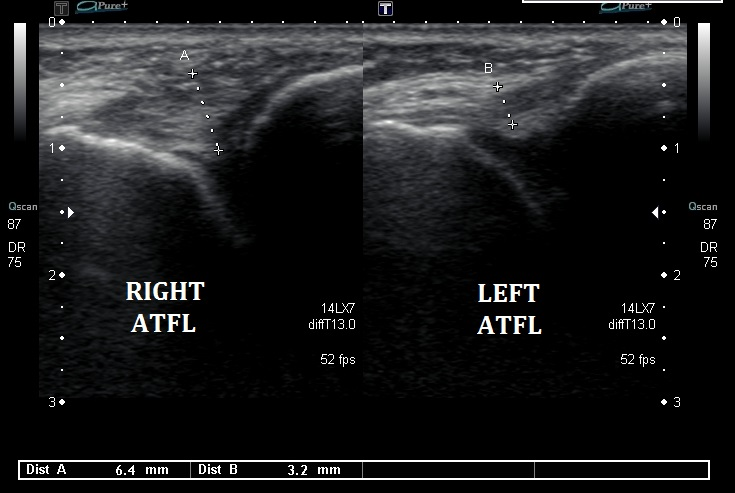

Le chiropracteur procède à des tests orthopédiques spécifiques pour évaluer la mobilité et identifier les ligaments touchés. En fonction des résultats, il pourra également vous prescrire une imagerie médicale, telle qu’une échographie et/ou une radiographie, afin d’identifier avec précision les structures en souffrance. Cela permet de visualiser les éventuels dommages ligamentaires, tendineux ou osseux, et d’ajuster le traitement en fonction de la gravité de la blessure.

• Échographie : Permet de visualiser les lésions ligamentaires et tendineuses.

Classification : Les grades des entorses

L’entorse de la cheville est classée selon trois grades, en fonction de la sévérité de la blessure et des structures ligamentaires atteintes :

• Grade 1 : Élongation ou déchirure minime des fibres ligamentaires. La douleur et l’enflure sont modérées, et la stabilité articulaire est conservée.

• Grade 2 : Déchirure partielle du ligament avec douleur, enflure importante et instabilité articulaire modérée.

• Grade 3 : Rupture complète du ligament. L’instabilité est marquée, avec une douleur et une enflure très importantes.